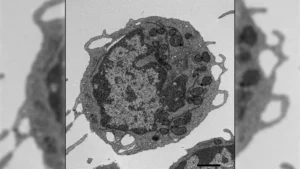

NK cells are a type of cytotoxic lymphocyte that play a vital role in innate immunity, capable of directly killing infected or cancerous cells without prior sensitization. Their inherent ability to target tumor cells, coupled with a generally lower risk of causing graft-versus-host disease (GVDHD) compared to T cells, makes them an attractive candidate for CAR-based immunotherapy. However, optimizing CAR-NK cell therapy presents unique challenges. Scientists are continually working to unravel the complex internal signaling pathways that govern NK cell function and to identify the most effective ways to enhance their cytotoxic potency and persistence within the tumor microenvironment.

The Brazilian research team has directly addressed this knowledge gap by investigating the impact of specific intracellular signaling mechanisms on CAR-NK cell activity. Their study centered on the NK-92 cell line, a well-established and widely used human NK cell line for research purposes. The researchers designed novel CARs that included critical costimulatory components, namely the 2B4 and DAP12 signaling pathways.